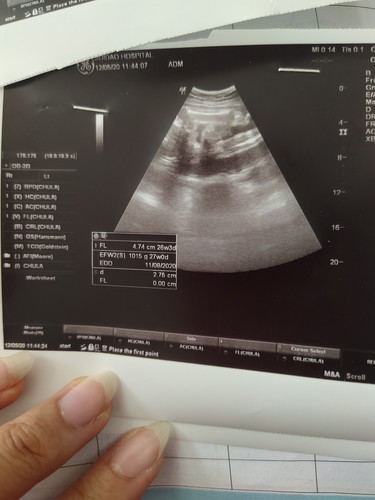

คืออายุครรภ์เรา 31week1day แต่ในใบซาวน์มัน26 week หมอบอกว่าน้ำหนักลูกน้อยเกินไป ต้องส่งไปตรวจโรงพยาบาลใหญ่

ต้องดูจากครั้งแรก ด้วยค่ะ แต่26กับ31 ห่างกันมากเกินไปค่ะ ทุกทีถ้าห่างประมาณ1w หมอยังไม่ว่าอะไรค่ะ